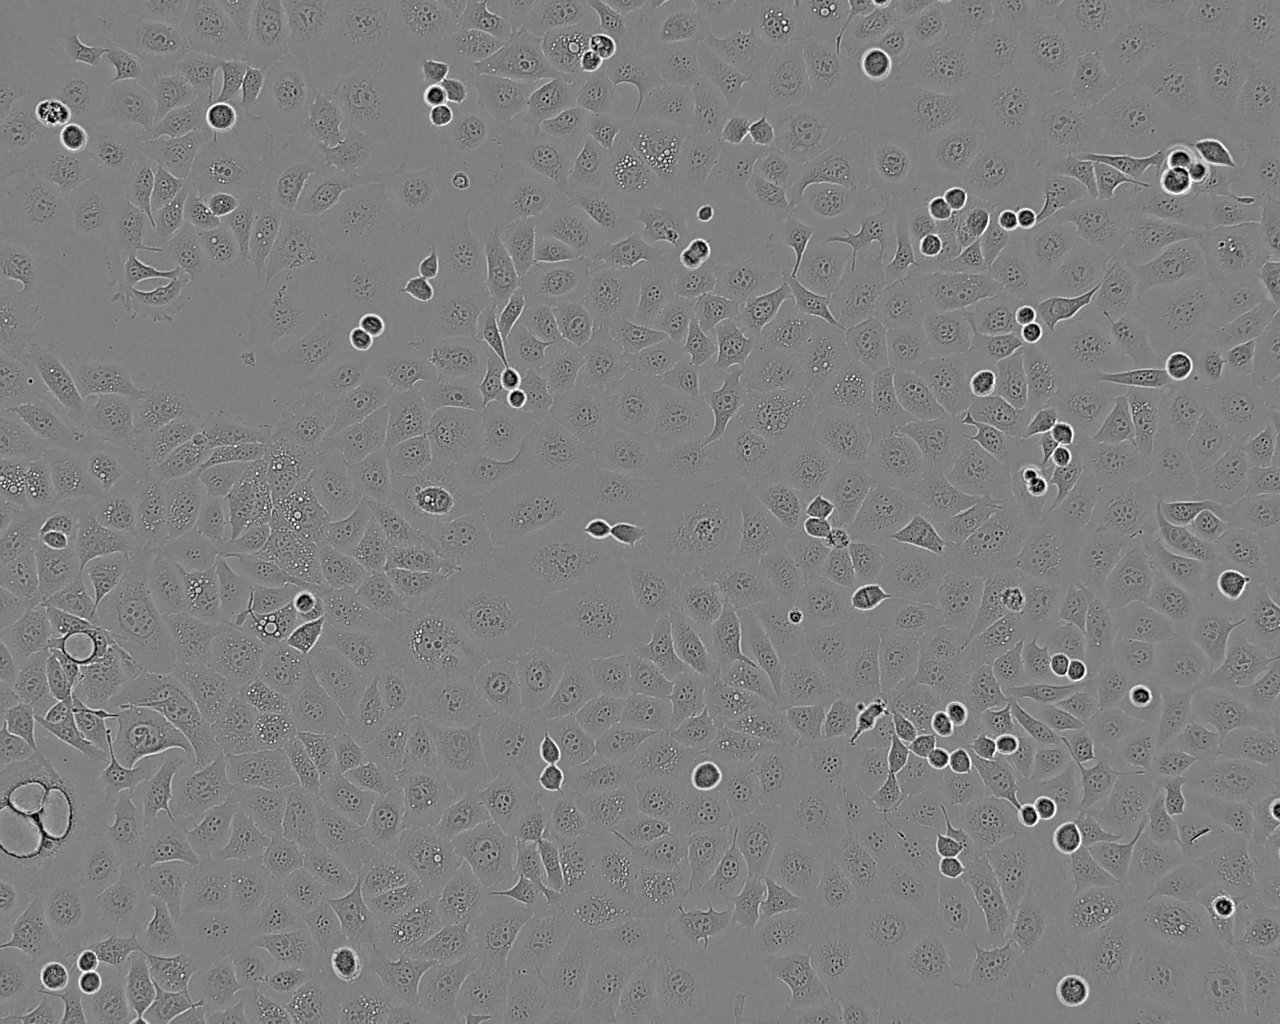

KYSE-30 was established from the oesophageal cancer of an untreated 64 year old male. The tumour sample was taken from the mucosal surface of a well differentiated squamous cell carcinoma. The cell line KYSE-30 was established with the use of tumours initially transplanted to athymic mice. The cells are reported to have a doubling time of 20.8 hrs in the exponential growth phase. A p53 mutation at the splice acceptor site of intron 6 and a 12 fold amplification of c-erb B has been reported. KYSE-30 cells express a large number of epidermal growth factor receptors, 1.2x10,000,000 sites/cell.

Morphology

Endothelial-like

Adherent